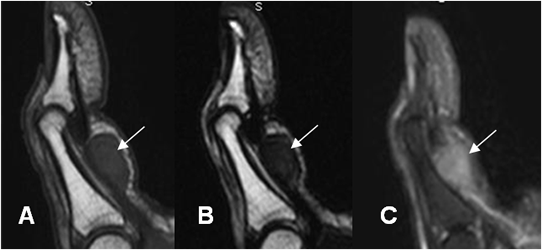

Fig 113. Enfermedad de Dupuytren.

A: RM sagital en T1, B: RM sagital en T2 y C: RM sagital en STIR. Deformidad en flexión del dedo, con imagen ovalada que se relaciona con el mecanismo flexor. Esta lesión es hipointensa en T1 y T2 e hiperintensa en STIR, por el componente fibroso y corresponde a enfermedad de Dupuytren.